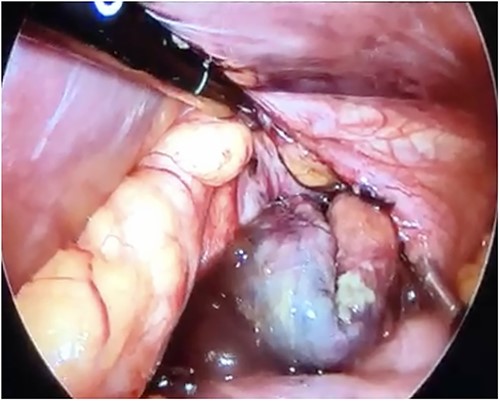

Initial treatment included intravenous crystalloid fluid repositioning, pain management, and antibiotic therapy. After diagnosing perforated gastric volvulus on a computed tomography (CT) scan, a diagnostic laparoscopy was performed. A hiatal hernia was identified with protrusion and twisting of the gastric body (Fig. 2). As the stomach body was reduced back to the abdominal cavity, a 1.5-cm perforation at the level of the greater curvature was detected. It was primarily sutured and covered with an omental patch (Fig. 3). The ischemic hernia sac containing the stomach was filled with food scraps and resected (Fig. 4). Laparotomy conversion was necessary due to hemodynamic instability attributable to the laparoscopic pneumoperitoneum. A 180° anterior fundoplication of the stomach (Dor’s Technic) associated with diaphragmatic raffia was performed. Gastric air leak testing was negative and intraoperative endoscopy showed no other defects on the gastric wall.

Laparoscopic view of the necrotic hernial sac with food scraps inside.